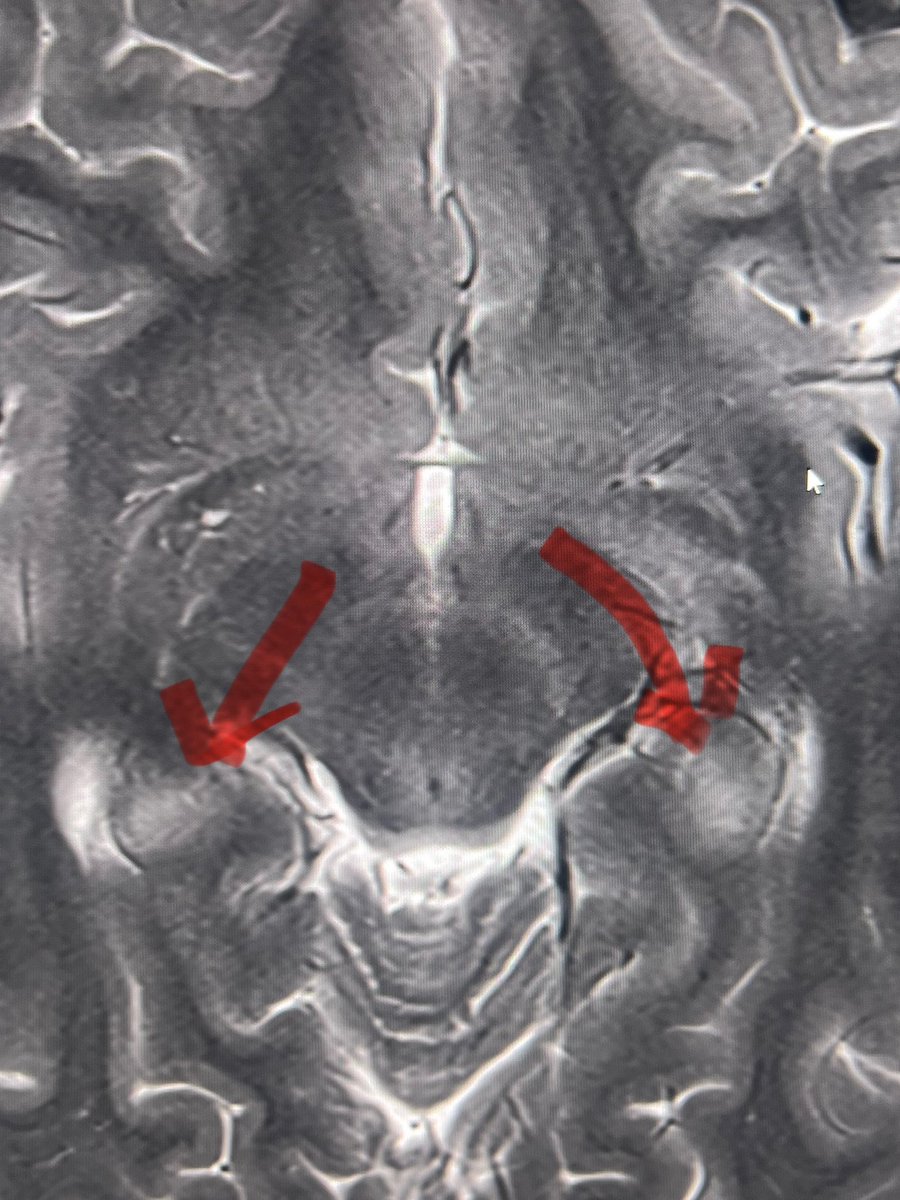

Tip of the day 💡: If CT is all one has, there is still a lot that can be gained- look out for the relative hyperdensity of cortical malformation. This was confirmed months later on an MRI scan. As a good diagnostician, use all you have- resources may be scarce, but human